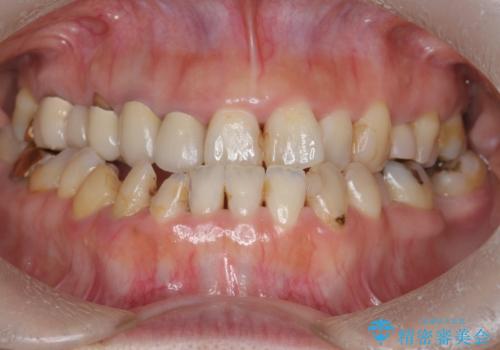

総合歯科治療

インプラント治療&セラミック治療掲載症例数197件

インプラント治療&矯正歯科治療掲載症例数37件

インプラント&根管治療&矯正歯科掲載症例数7件

根管治療&セラミック治療掲載症例数205件

根管治療&矯正歯科治療掲載症例数8件

歯周病治療&インプラント治療掲載症例数74件

歯周病治療&セラミック治療掲載症例数192件

歯周病治療&矯正歯科治療掲載症例数22件